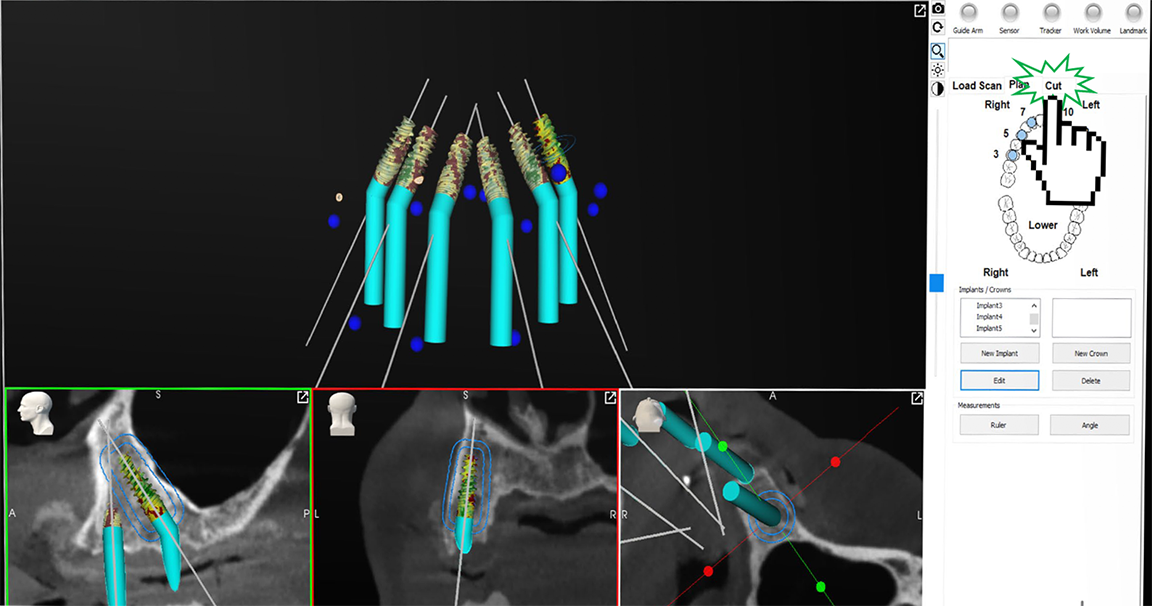

Robotic-assisted dental surgery combines the advantages of both the physical constraints of static guides and the flexibility of image-based dynamic navigation. Haptic technology allows the practitioner to move the robotic handpiece just as he or she would move a traditional handpiece, with the added benefit of physical feedback that provides extra guidance. Robotic assistance provides 3D physical guidance of the dental surgical instruments during execution of the digital plan in terms of the desired location, angulation, and depth of the osteotomy. Surgery is performed through the robot, precisely as it was designed in the virtual world without static guides. The practitioner gets a visual readout, with coordinate data input to the robot, without having to lift his or her eyes from the surgical field. Predicted results seen on-screen become reality. The use of robotics minimizes stack-up errors commonly found with static guides and while utilizing the practitioner's familiarity with digital planning and surgical and restorative processes. Practitioners build rapport with patients through delivering on promises made, increasing patient confidence, and providing esthetically satisfying and functional restorations.2-4

Going from virtual to reality, topographical landmarks on the bony surfaces are used as 3D blueprints for implant planning. Every bit of information needed is on the screen (Figure 14) and is verified, allowing rendering of a surgical result with a degree of precision not possible with computer-based planning. Regardless of how complicated the implant planning, the practitioner can concentrate on the oral cavity with the computer screen providing the reference points.2-4

Fig 14. Topographical landmarks on the bony surfaces are used as 3D blueprints for implant planning.

Figure 14